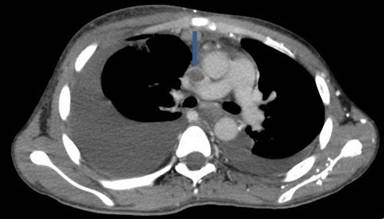

A 30-year-old man presented to our outpatient clinic with history of abdominal distention without pedal edema for the past 3 months. He also had deep boring epigastric pain and vomiting for 2 months. He had noticed low grade fever and anorexia for last 15 days. He had been consuming alcohol (100 g/day) for last 5 years (last drink 3 months back). Examination revealed pallor, facial puffiness, tachycardia, ascites and bilateral pleural effusion. His neck veins were engorged and hepatojugular reflex was absent. On investigation ascitic fluid was hemorrhagic with proteins 5.5 g/dL (reference range: 0-0.5 g/dL); white blood cells were 215 mm-3 (reference range: 0-5 mm-3; polymorphs 35% and lymphocytes 65% in a background of red blood cells). Ascitic fluid adenosine deaminase was 20 IU/mL (reference range: 0-35 IU/mL) and ascetic fluid amylase 58,840 IU/L (reference range: 0-100 IU/L). Pleural fluid was also hemorrhagic with protein 5.5 g/dL (reference range: 0-0.5 g/dL), white blood cells 80 mm-3 (polymorphs 50%, lymphocytes 50%) and adenosine deaminase was 35 IU /mL. 2D echo was normal. Serum amylase was 700 IU/L (reference range: 0-150 IU/L), serum lipase was 3,526 IU/L (reference range: 0-150 IU/L), and pleural fluid amylase was 5,748 IU/L (reference range: 0-50 IU/L). CT scan showed thromboses of bilateral subclavian and internal jugular vein, superior vena cava, infra renal inferior vena cava, a segment of suprarenal and infrahepatic inferior vena cava and right common iliac vein and patent splanchnic veins (Figures 1-5). Color Doppler abdomen showed normal portal vein of 10 mm diameter with hepatopetal flow, normal retrohepatic inferior vena cava with hepatopetal flow, while rest of inferior vena cava was thrombosed; all three hepatic veins well visualized with normal flow (Figure 6). MRCP revealed acute inflammation with underlying chronic pancreatitis with stricture at junction of head and body with intraductal calculi with leak at head and body junction and multiple loculated intra abdominal collections. The prothrombotic work up, including factor V Leiden, JAK 2 mutation, homocysteine, antiphospholipid antibody, protein C and S, and antithrombin III, was negative. Thus, a diagnosis of chronic pancreatitis with pancreatic ascites and pleural effusion with multiple extrasplanchnic thromboses due to pancreatitis was made. Patient was managed conservatively with intravenous heparin, initially continuous infusion of 1,000 units/hour and later on oral anticoagulants. ERCP with pancreatic sphincterotomy was done and a 5Fr x 10 cm stent was placed. Patient symptomatically improved with complete disappearance of ascites. His repeat color Doppler showed partial recanalization of superior vena cava, internal jugular vein and subclavian veins (Figure 7).

Figure 5. CECT axial view depicts thrombosis of superior vena cava (arrow) with bilateral pleural effusion (right more than left). |